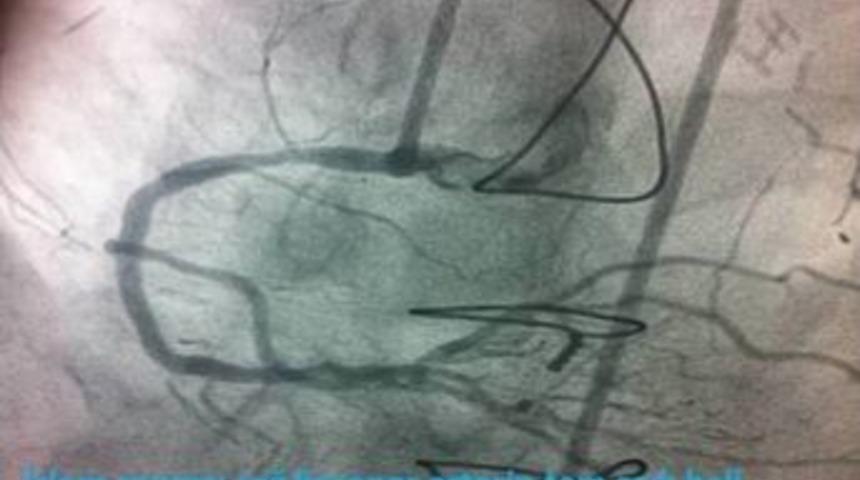

Balıkesir Üniversitesi (BAÜ) Sağlık Uygulama ve Araştırma Hastanesi'nde uzun dönem yüzde 100 tıkalı kalan koroner kalp damarı ameliyatsız bir şekilde açıldı.

Kardiyoloji Anabilim Dalı öğretim üyeleri Yrd. Doç. Dr. Erkan Ayhan ve Yrd. Doç. Dr. Turgay Işık, tarafından gerçekleştirilen işlem, ameliyat gereksinimi olmadan klinikte başarılı bir şekilde uygulandı.

Sağlık Uygulama ve Araştırma Hastanesi Kardiyoloji Anabilim Dalı öğretim üyes Yrd. Doç. Dr. Ayhan, Türkiye'de belirli kalp merkezlerinde uygulanan işlemin, Balıkesir'de ilk kez üniversite hastanesinde uygulandığını söyledi. Bu işlemin uzun dönem koroner damarları tam tıkalı kaldığı halde canlılığını korumuş kalp dokusuna sahip bireylerde yapıldığını bildirdi.

Hastalarda inatçı göğüs ağrısı gibi yakınmaları gidermeye faydalı olan bu yöntemin, bilinen stent işleminden farklılıkları olduğuna işaret eden Ayhan, hastaya genel anestezi verilmediğini ve hastanede kalış süresinin operasyona göre daha kısa olduğunu vurguladı. Hastaların fazla vakit kaybetmeden bu işlemi yapan kliniklere başvurmasının önemine değindi.